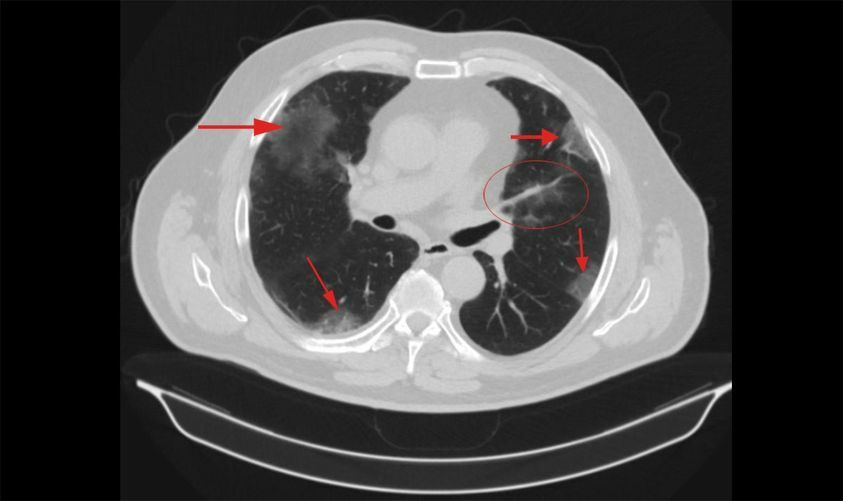

Форум после кт

Форум после кт 80 фото